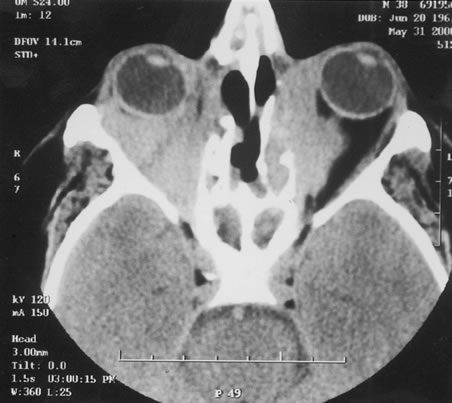

The finding of retinal vascular changes in patients with SLE correlates with the activity of the disease.214 The relationship of cotton-wool spots alone to CNS lupus has been debated, but to date no relationship has been established. Most experts feel that the finding of cotton-wool spots does not indicate the presence of CNS lupus. A much less frequent, severe retinal vasoocclusive disease has been described and does appear to be associated with CNS lupus, in particular, diffuse CNS dysfunction, such as an organic brain syndrome.214–223 This more severe retinal vasoocclusive disease may present as a central retinal artery occlusion, central retinal vein occlusion, branch artery occlusion, or most frequently, a diffuse retinal vasoocclusive process (Fig. 5), sometimes called retinal vasculitis. Although this last process sometimes has been called retinal vasculitis, the exact pathogenesis may not be true vasculitis. Cases of severe retinal vasoocclusive disease in SLE in association with the lupus anticoagulant also have been reported, and the retinal disease in these cases is presumed to be secondary to this autoantibody (Fig. 6).190,191 The prognosis for vision with this diffuse retinal vascular disease is poor and retinal neovascularization commonly develops. Panretinal photocoagulation may be of value in the treatment of the neovascularization of severe lupus retinopathy. Approximately 50% of eyes affected with this severe vaso-occlusive disease become blind. Although visual loss is common in those patients with severe retinal disease, in the more common mild retinopathy visual loss is unusual.223

Fig. 5. A. Fundus photograph and B. fluorescein angiogram, demonstrating diffuse vaso-occlusive disease in a patient with systemic lupus erythematosus. Fluorescein angiogram shows extensive nonperfusion of the retina. (Jabs DA, Fine SL, Hochberg MC, et al: Severe retinal vaso-occlusive disease in systemic lupus erythematosus. Arch Ophthalmol 1104:558, 1986. Copyrighted 1986, American Medical Association. Reprinted with permission.)

Fig. 6. A. Fundus photograph and B. fluorescein angiogram demonstrating diffuse vaso-occlusive disease in a patient with systemic lupus erythematosus. This is peripheral nonperfusion of the retina. The patient had anticardiolipin antibodies. (Jabs DA, Fine SL, Hochberg MC, et al: Severe retinal vaso-occlusive disease in systemic lupus erythematosus. Arch Ophthalmol 104:558, 1986. Copyrighted 1986, American Medical Association. Reprinted with permission.)